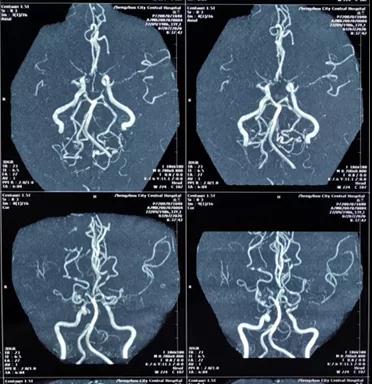

烟雾病属于脑血管病的一种,又称自发性颅底动脉环闭塞症,是以颈内动脉末端及大脑前或中动脉起始部动脉内膜缓慢增厚,动脉管腔逐渐狭窄以至闭塞,脑底穿通动脉代偿性扩张,形成异常毛细血管网为特征的慢性脑血管疾病。因在血管造影中,脑底的异常血管形状酷似吸烟时吐出的烟雾,故称为烟雾病。

完善了术前准备后,贾映海教授和四川省人民医院黄光富教授强强联手,为赵女士实施了STA-MCA(颞浅动脉 - 大脑中动脉)搭桥术,用一根比头发丝儿还细的针线在直径仅仅1mm的血管上进行搭桥。